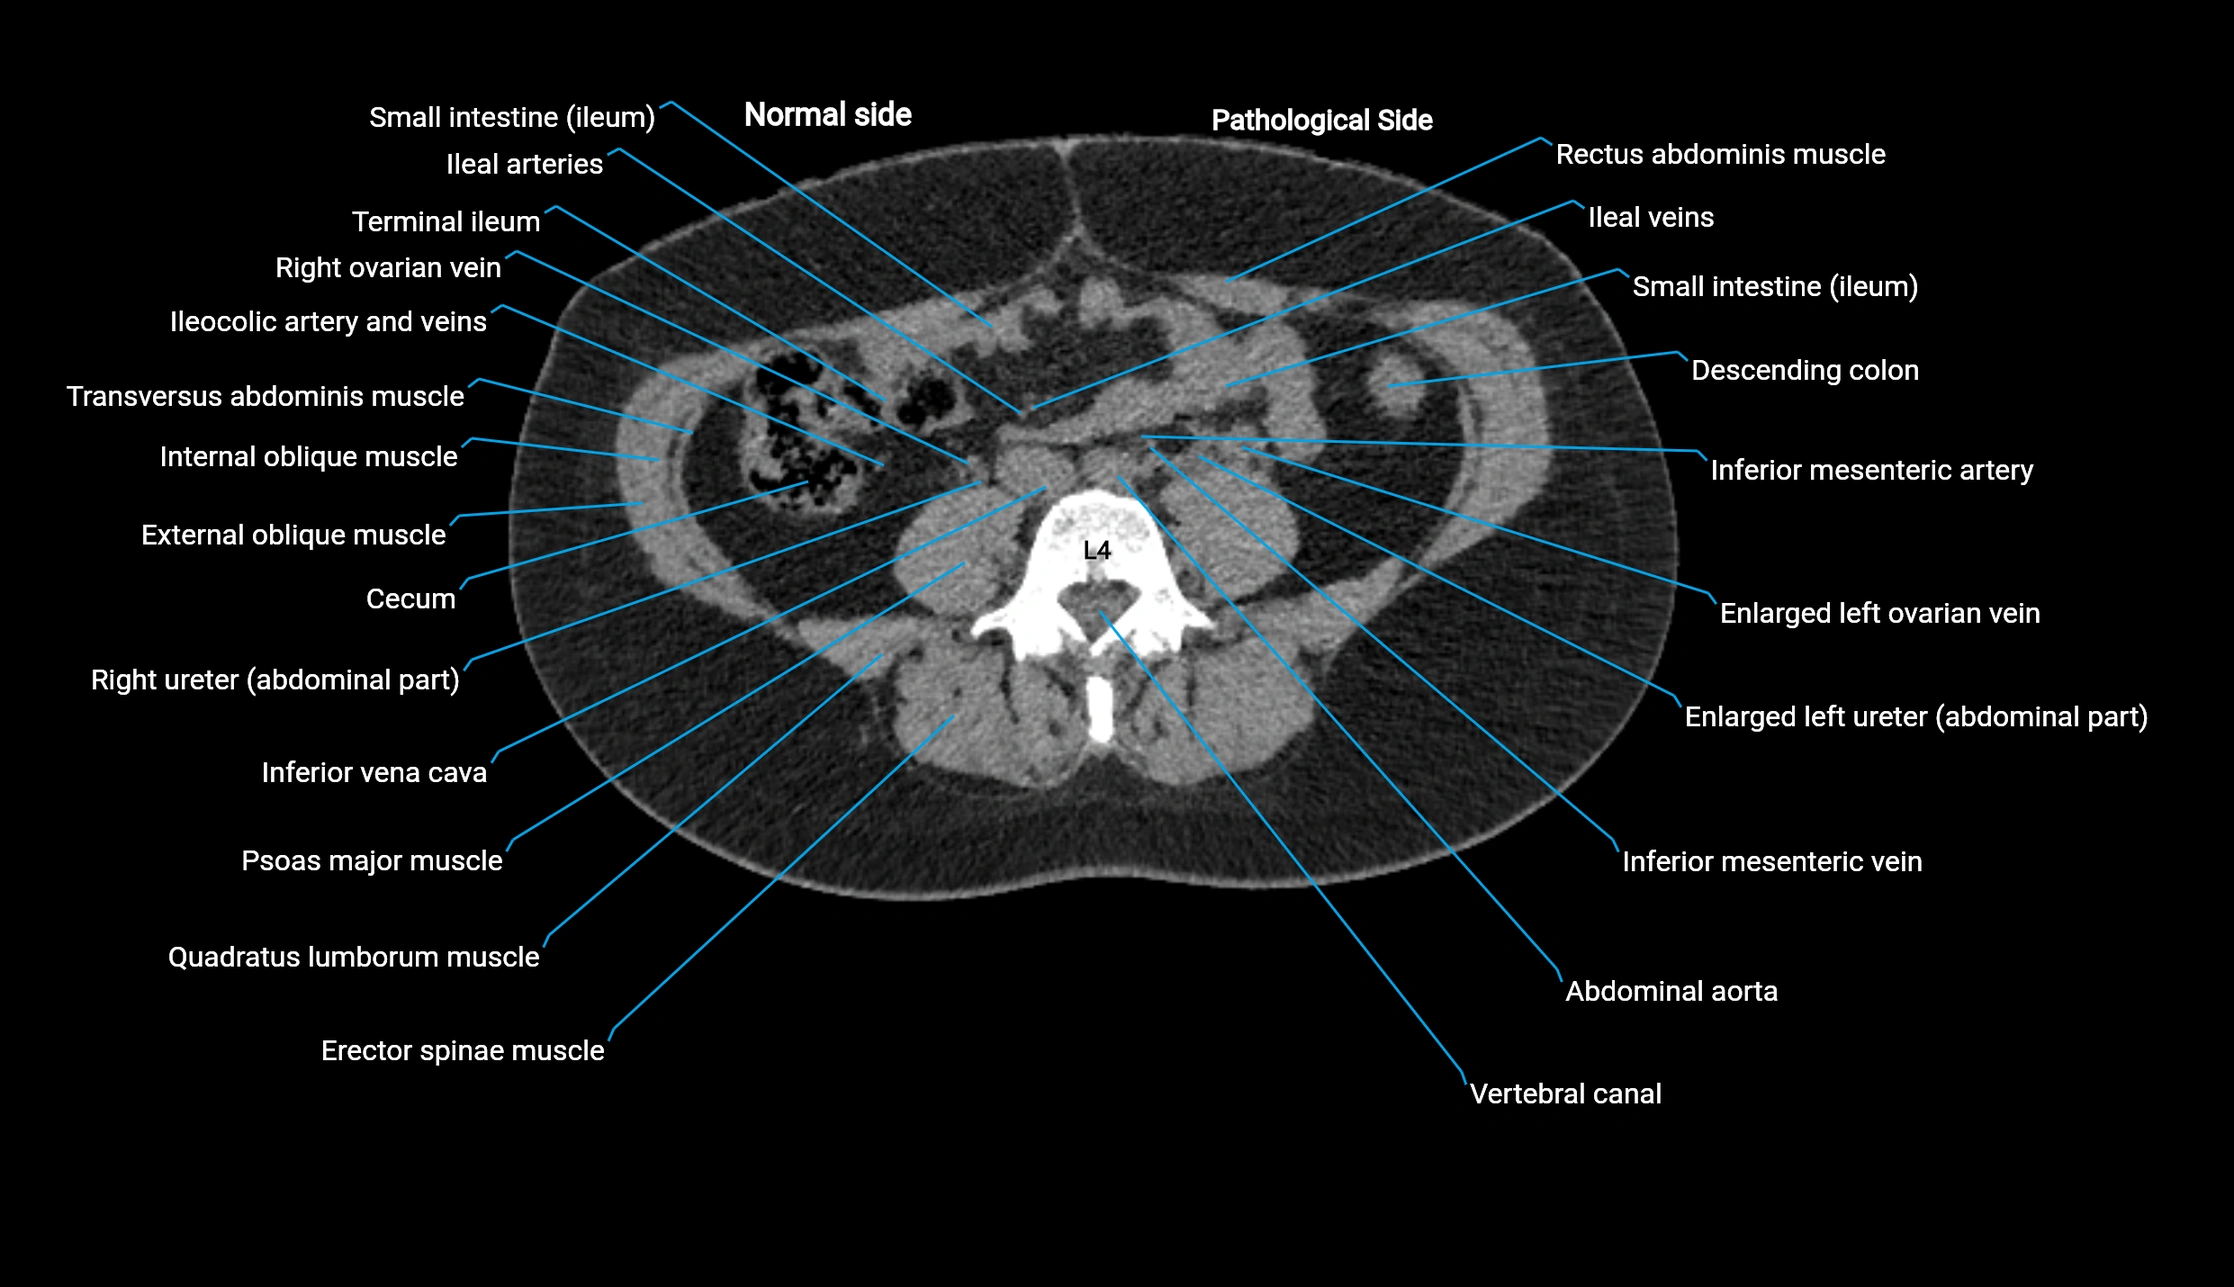

CT image

image